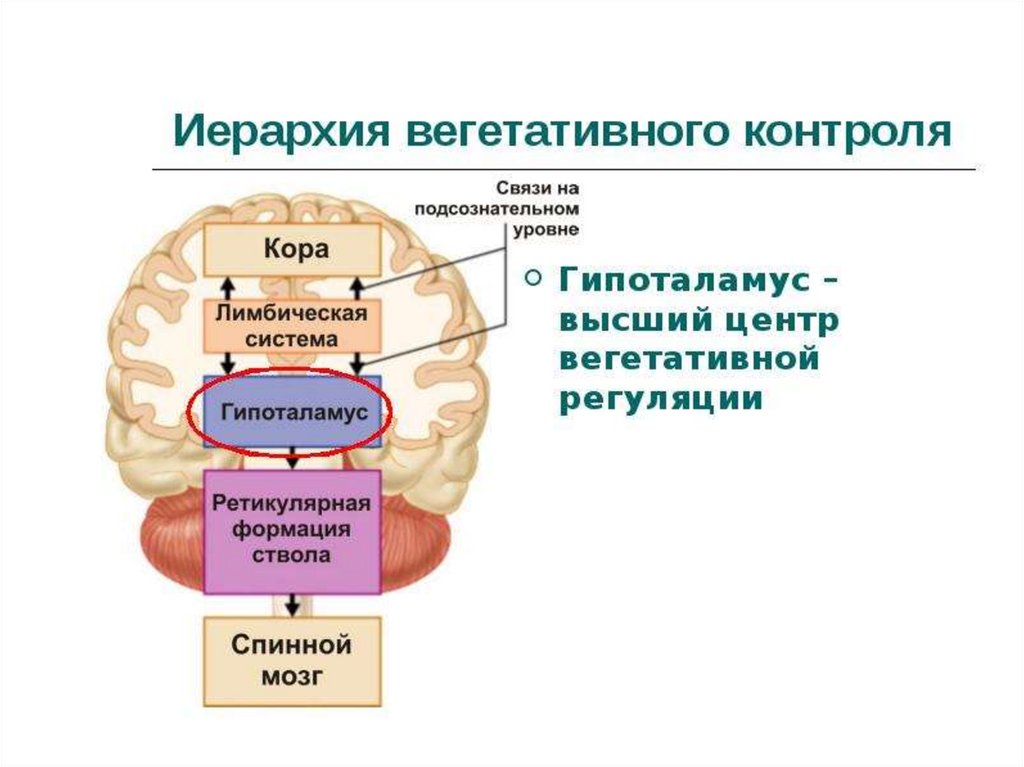

Как работает центр насыщения в гипоталамусе: визуальные иллюстрации